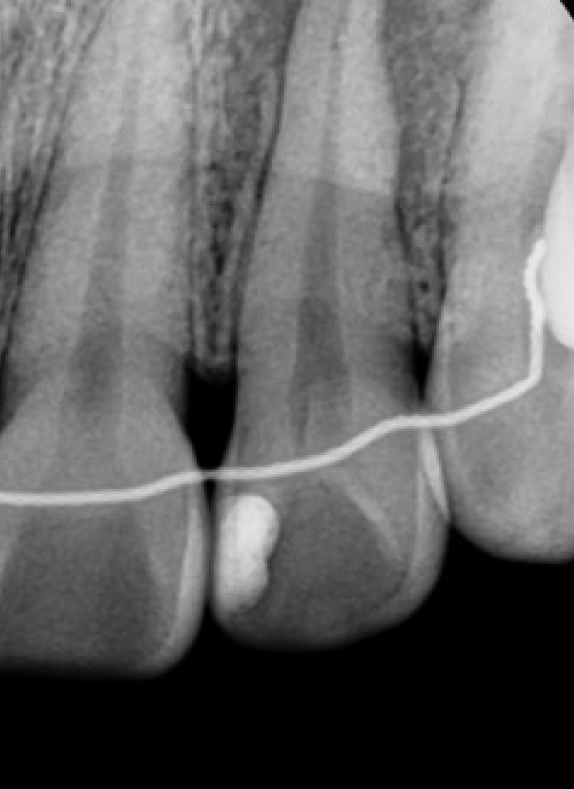

엑스레이 촬영 결과,

해당 치아의 치수(신경)가

이미 괴사된 상태였고

치아 뿌리 끝(치근단) 주변으로

어두운 음영이 보였습니다.